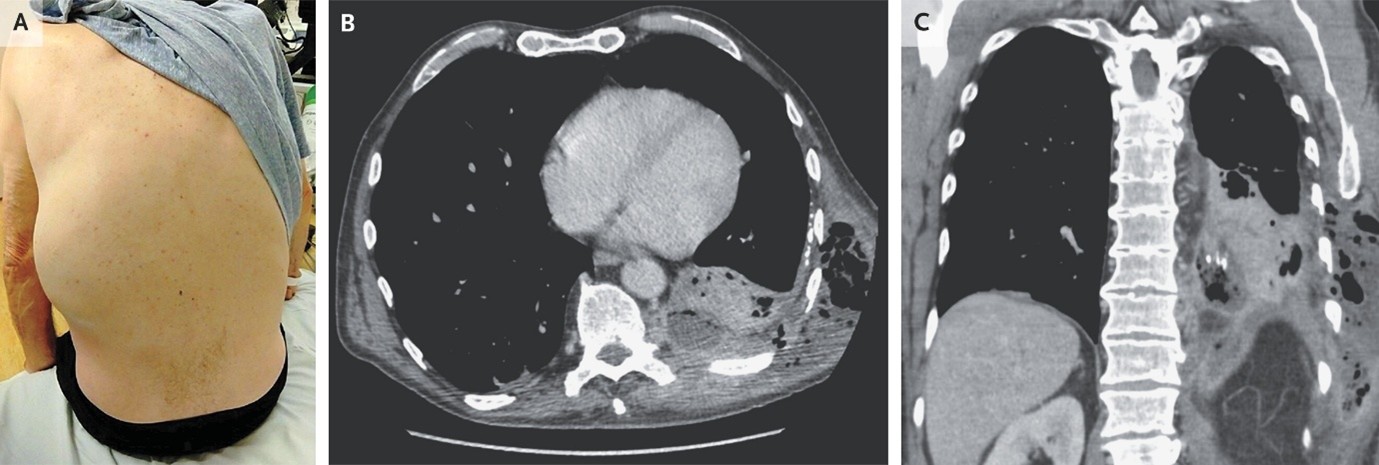

(8). Empyema Necessitans

Adeoluwa Ayoola, et al, published December 3, 2025,N Engl J Med 2025;393: e38,DOI: 10.1056/NEJMicm2504921,VOL. 393 NO. 22

Abstract

A 66-year-old man presented with 2 weeks of shortness of breath and cough, 5 days of left flank pain, and 2 days of a rapidly expanding mass on his left side.